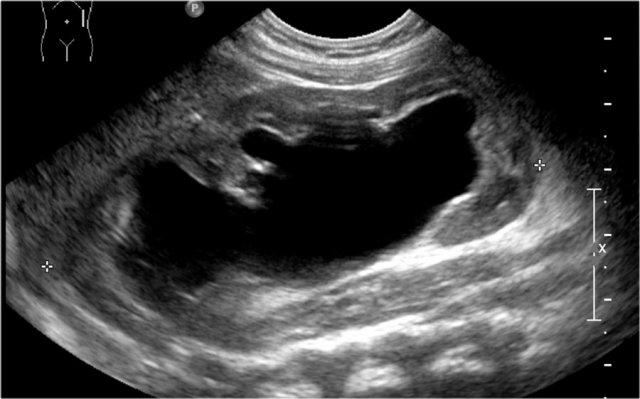

Một bé trai 1 tuổi được chuyển đến với chẩn đoán u nguyên bào thận dạng nang.

Siêu âm phát hiện một nang lớn ở trung tâm ổ bụng.

Khi khảo sát từ hông trái bằng đầu dò tuyến tính tần số cao, có thể thấy một ít mô nhu mô bao quanh các đài thận giãn rất to. Hình ảnh này phù hợp với ứ nước thận mức độ nặng.

Ban đầu, người ta cho rằng có một số thành phần đặc trong nang.

Tuy nhiên, khi ấn đầu dò, các thành phần này được xác định là cặn lắng.

MRI cho thấy hình ảnh tổng quan hơn về tình trạng ứ nước thận.

Nguyên nhân là do hẹp khúc nối bể thận – niệu quản.

Thận trái có chức năng phân chia 33% trên xạ hình thận.

Phẫu thuật tạo hình bể thận đã được thực hiện thành công.